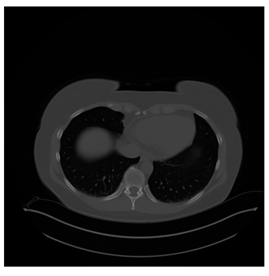

4.3. The Results

In this subsection, we describe three experiments used to measure the performance of the proposed method. The first experiment shows the stegoimage and marks the pixels’ positions that have been modified during the embedding process, as shown in Table 2, Table 3, Table 4, Table 5, Table 6 and Table 7. To make modified pixel positions have a pronounced effect, we set bpp (bit per pixel) rate at 0.05 and 0.025. It can be seen from the results that the proposed local complexity function can distinguish ROI and RONI from most of the medical images, so modified pixels are mainly gathered in RONI. However, it is observed that the proposed local complexity function cannot distinguish between ROI and RONI in the Prostate-MRI database due to the relative complexity of the image. Besides, “Modified BPP” represents the proportion of pixels in the image that have been modified. We observed that the performance of “baboon” in the grayscale standard images database is poor because that image’s pixels are relatively complex. It becomes challenging to select the more embeddable pixels based on the proposed local complexity function. Nevertheless, the modified pixel positions in other grayscale standard images, such as Lena and Barbara, are relatively smooth, verifying that our local complexity function is also applicable to general images.